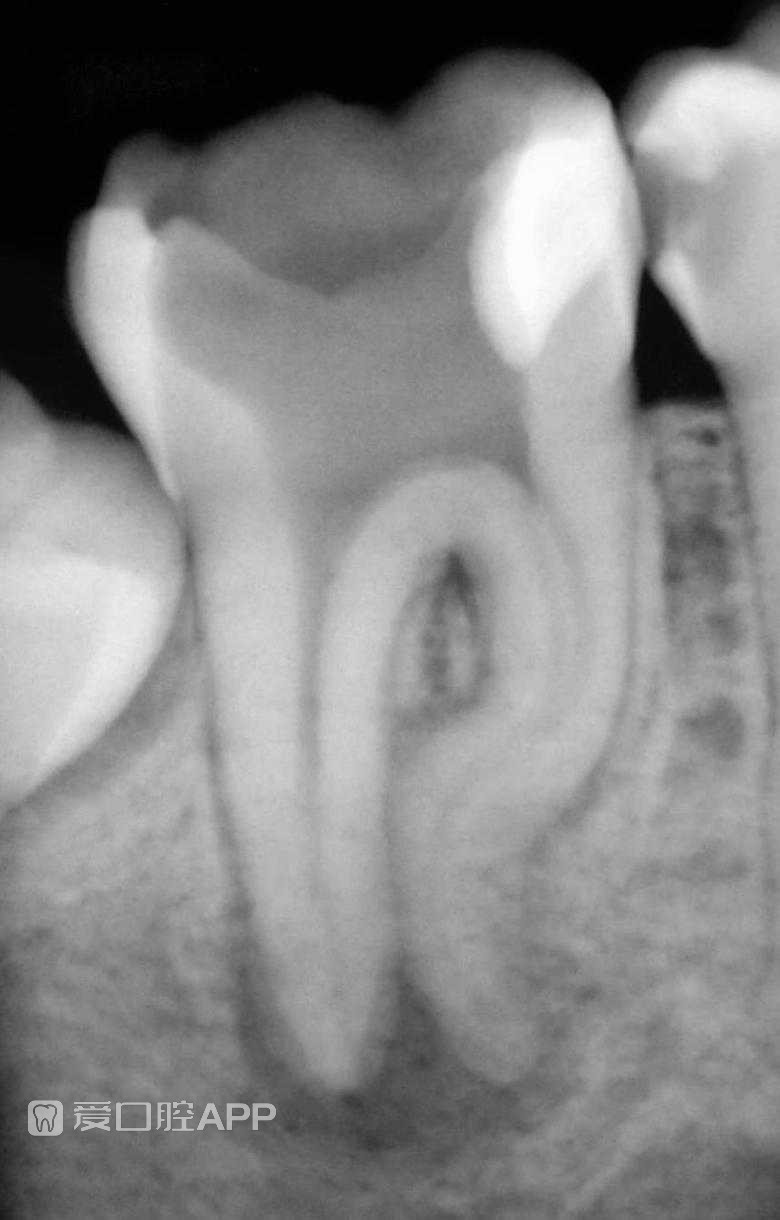

看个根充 —— 右下7

牙医:发炎就发炎,还翘个二郎腿